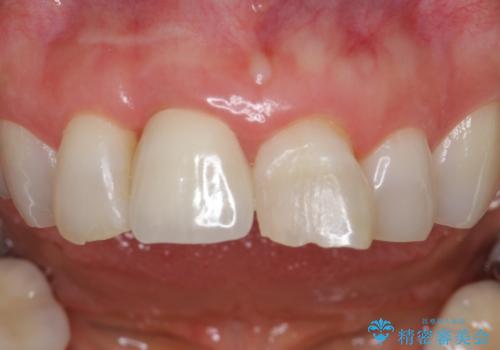

ぶつけて埋まってしまった歯は、場合によって矯正治療で引っ張り出すことで保存することができます。

今回は歯の神経が死んでしまっていたため、根管治療後に被せ物を装着して見た目の綺麗さを回復しました。